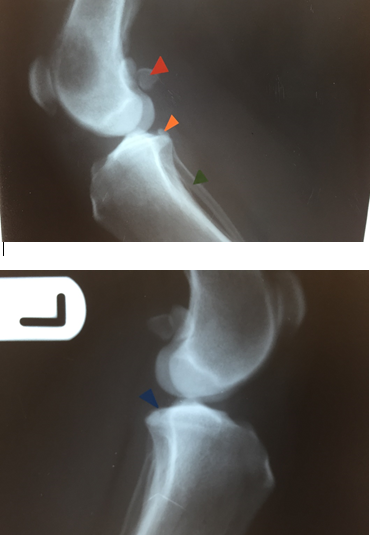

On this radiograph:

Identify the labelled bone orange, red and blue.

Identify the labelled bone orange, red and blue. [Answer:

orange=humerus

blue=ulna

red=radius

Label anconeal process

Label medial coronoid process